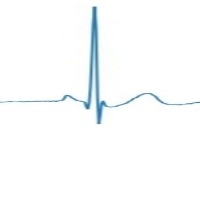

Couplet Computer Vision Project

Cardiac Monitoring: Couplet can be incorporated into patient monitoring systems to detect the various types of couplets in real-time, allowing healthcare professionals to identify arrhythmias and other cardiac anomalies. Early intervention can lead to better patient outcomes.

Telemedicine: Couplet can be integrated into telemedicine platforms to remotely assess a patient's electrocardiogram (ECG) signals. This helps improve access to care for patients who live in rural or hard-to-reach areas, allowing physicians to review their ECG and determine if there are any issues that require immediate attention.

Wearable Device Analysis: Couplet can be embedded into wearable health devices, such as smartwatches or fitness trackers, to analyze ECG data in real-time. This can help users monitor their heart health and alert them to any abnormalities, encouraging proactive healthcare management.

Medical Research: Couplet can be used by researchers studying the prevalence and causes of various couplet types. Automating the identification process can save time and improve accuracy, allowing researchers to focus on understanding the underlying mechanisms and developing effective treatments.

Medical Training and Education: Couplet can be applied to educational materials and training modules, helping medical students and professionals learn to identify different couplet types. By automating the recognition process, trainees can test their skills and gain confidence in their ability to diagnose conditions related to couplet classes.